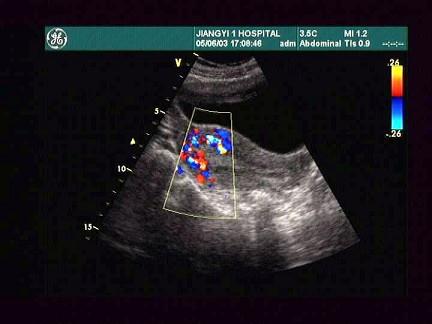

女,24岁,人流术1个月后阴道不规则出血。根据超声所示,应考虑为?(?)A.宫内残留B.葡萄胎C.绒癌D.早孕E.子宫肌瘤

问题 女,24岁,人流术1个月后阴道不规则出血。根据超声所示,应考虑为?(?)

选项 A.宫内残留 B.葡萄胎 C.绒癌 D.早孕 E.子宫肌瘤

答案 A